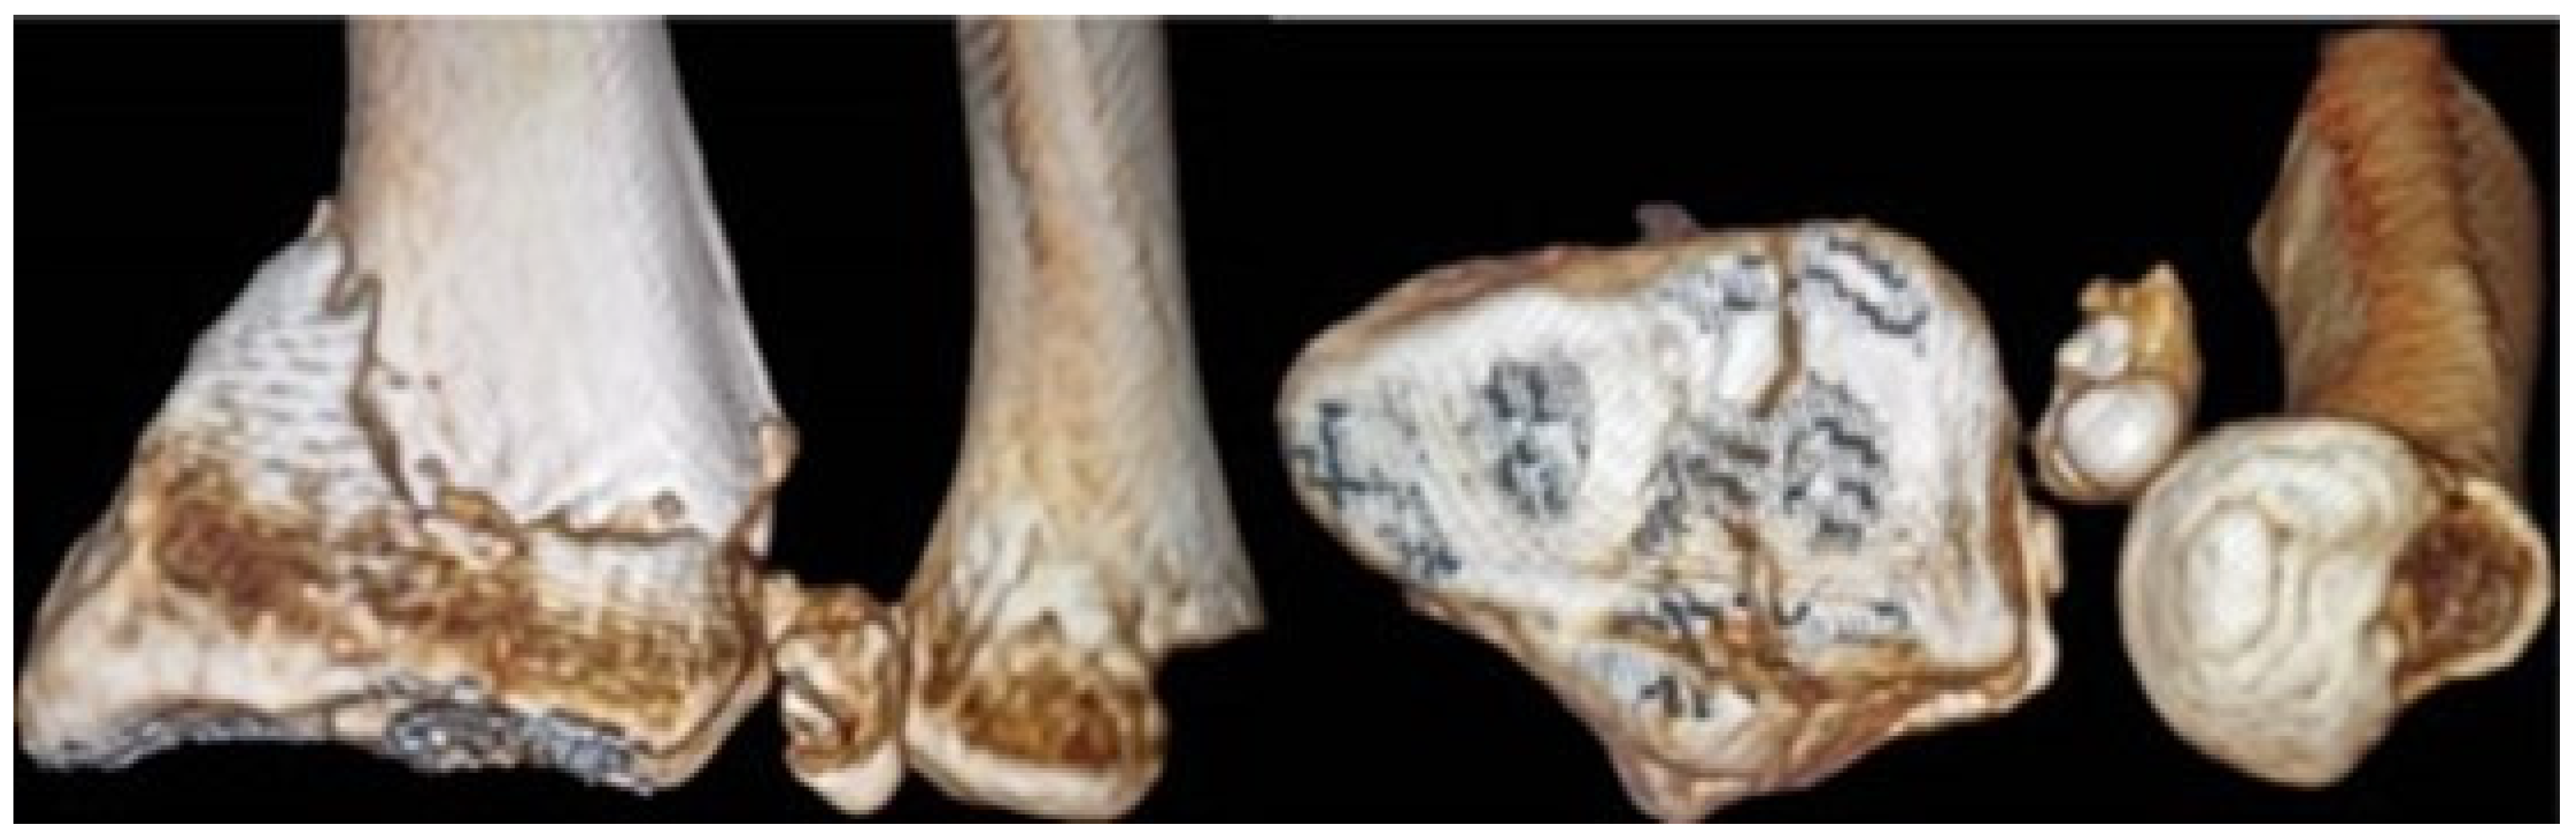

| Galeazzi fractures | High-energy trauma | Clinical presentation: forearm swelling, deformity [60]. Imaging: X-rays, CT scans [7]. | Surgical intervention: ORIF, DRUJ stabilization [7,65,66], postoperative care and rehabilitation. Complications may include persistent pain, stiffness, instability [60]. | Comprises approximately 7% of all forearm fractures [61]. |

5.1. Conventional Radiography